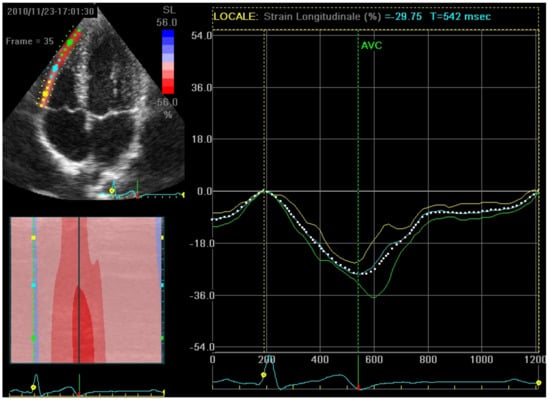

STE is often used to assess LV function using several parameters, among which is the longitudinal strain, which is the cardiac deformation directed from the base to the apex: negative curves imply a reduction in the distance between the kernels caused by myocardial fiber shortening from the base to the apex [11]. Longitudinal strain analyzed in 4-, 2- and 3-chambers can assess both regional and global strain (normal range is from −17.2% to −27.7%) [11,12]. As a result, during systole and shortening of the speckle-to-speckle distance, longitudinal strain values are displayed as negative curves (Figure 1) [10,11,12].

Figure 3. Top left: a RV free-wall in a 4-chambers view divided into three segments by the STE software, each providing its own longitudinal strain value. Right: the curve of each segment’s longitudinal strain and the average curve representing RVFWLS. RV: right ventricle; STE: speckle tracking echocardiography, RVFWLS: right ventricle free-wall longitudinal strain.